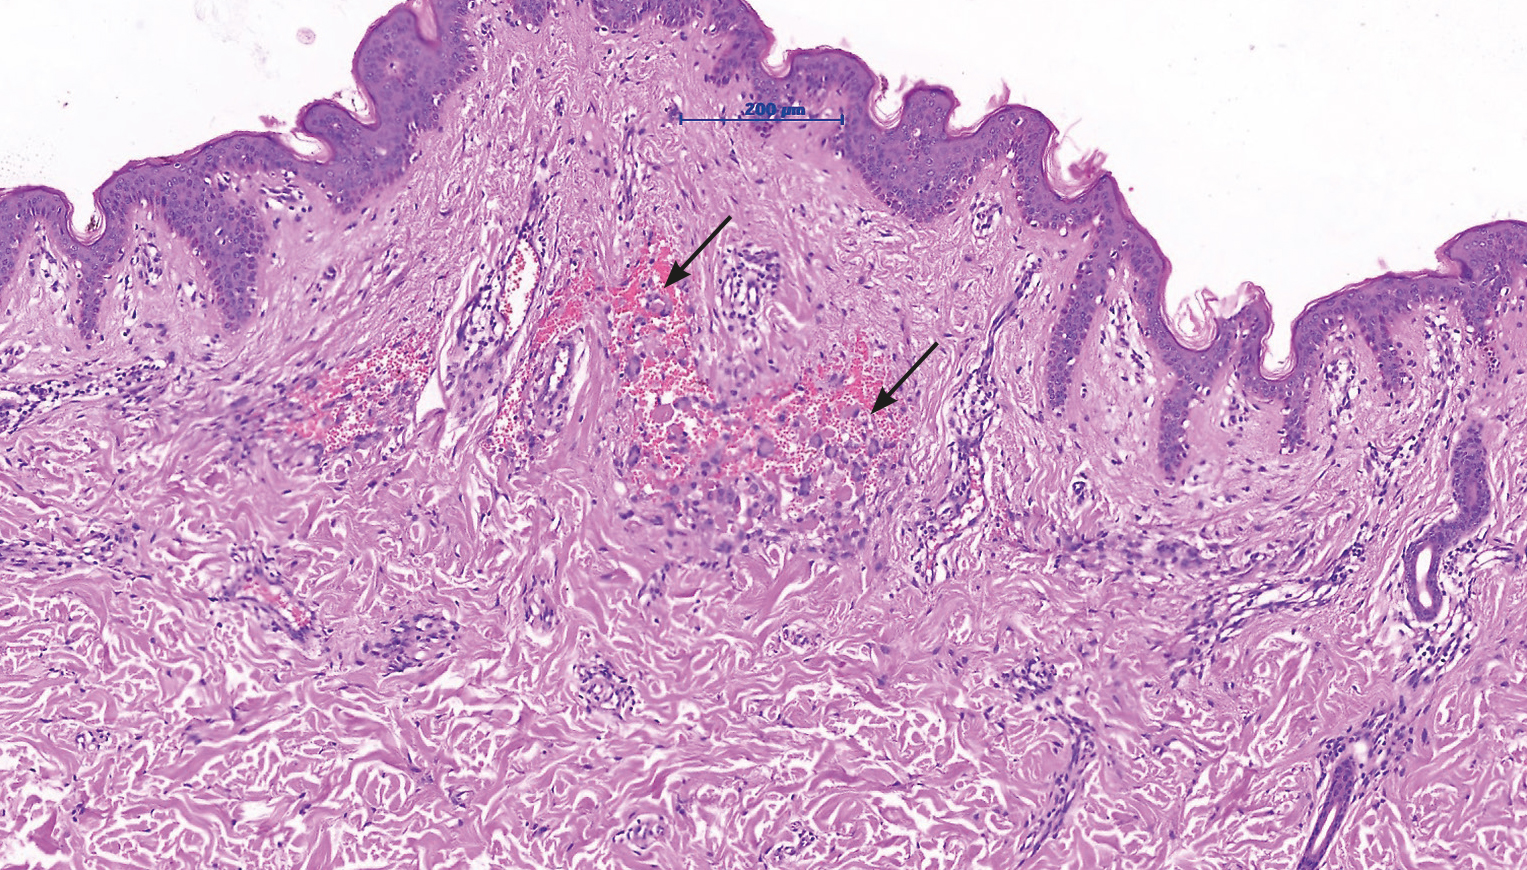

Лабораторно-инструментальная диагностика. Результаты проведённых исследований крови и мочи в пределах нормы. Результаты биохимического анализа крови свидетельствуют о некотором снижении уровня компонента C3 (73 мг/дл при норме 88–201). При гистологическом исследовании биоптата кожи, взятого из одной папулы, выявлено значительное увеличение количества расширенных и тромбированных сосудов в дерме, демонстрирующих пролиферацию по клубочковому типу. В некоторых сосудах обнаружены укрупнённые клетки со слабобазофильными ядрами и эозинофильной цитоплазмой, которые свободно расположены в просвете кровеносных сосудов (рис. 2). Кроме того, зафиксировано подкожное кровоизлияние. Значительное количество мононуклеарных клеток с периваскулярной и периаднексальной локализацией демонстрировали иммуногистохимическую реакцию на CD68 (KP-1), при этом не экспрессировали общие для лейкоцитов антигены CD3 и CD20 (рис. 3). Часть эндотелиальных клеток экспрессировала антигены CD31 и CD34. Сосуды оказались негативными на белок D2-40.

Рис. 2. Микроскопическое исследование (окрашивание гематоксилином и эозином, ×200): в сосочковом слое дермы определяются эктазированные полнокровные сосуды капиллярного типа с наличием в просвете групп тесно расположенных гистиоцитов с базофильными ядрами и эозинофильной цитоплазмой (стрелки). [Фото из архива РНИМУ им. Н.И. Пирогова. Публикуется впервые с разрешения администрации учреждения].

Fig. 2. Microscopic examination (staining with hematoxylin and eosin, ×200): in the papillary layer of the dermis, ectatized, full-blooded capillary-type vessels are detected with the presence of groups of closely spaced histiocytes with basophilic nuclei and eosinophilic cytoplasm in the lumen (arrows). [Photo from the archive of the Russian National Research Medical University named after N.I. Pirogov. Published for the first time with the permission of the administration of the institution].